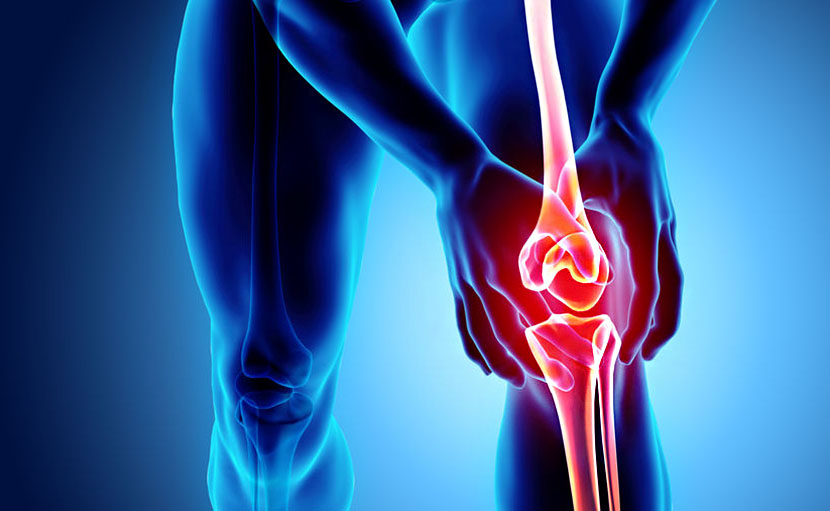

হাঁটুর ব্যথা কমাতে ৩টি কার্যকরী ইয়োগা

0 SHARES Share Tweet বর্তমানে হাঁটুর ব্যথা যেন আমাদের নিত্যদিনের সঙ্গী। কমবেশি সকলকেই হাঁটুর ব্যথায় আক্রান্ত হতে দেখা যা...